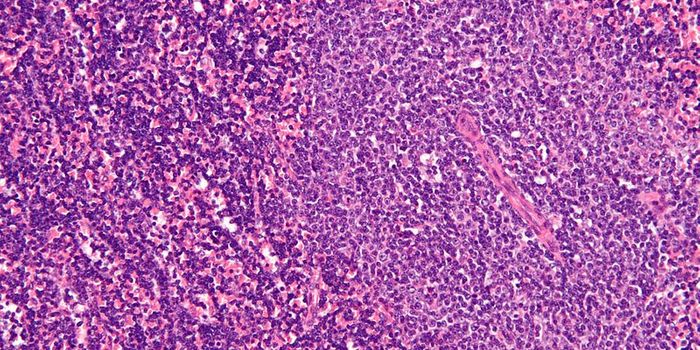

FEB 12, 2016ImmunologyAcute lymphoblastic leukemia (ALL) and non-Hodgkin’s Lymphoma (NHL) affect 75,000 and 72,000 people each year in t ...

MAR 18, 2015Immunology

After a chance observation in the lab, researchers found a method that can force dangerous leukemia cells in the l ... -